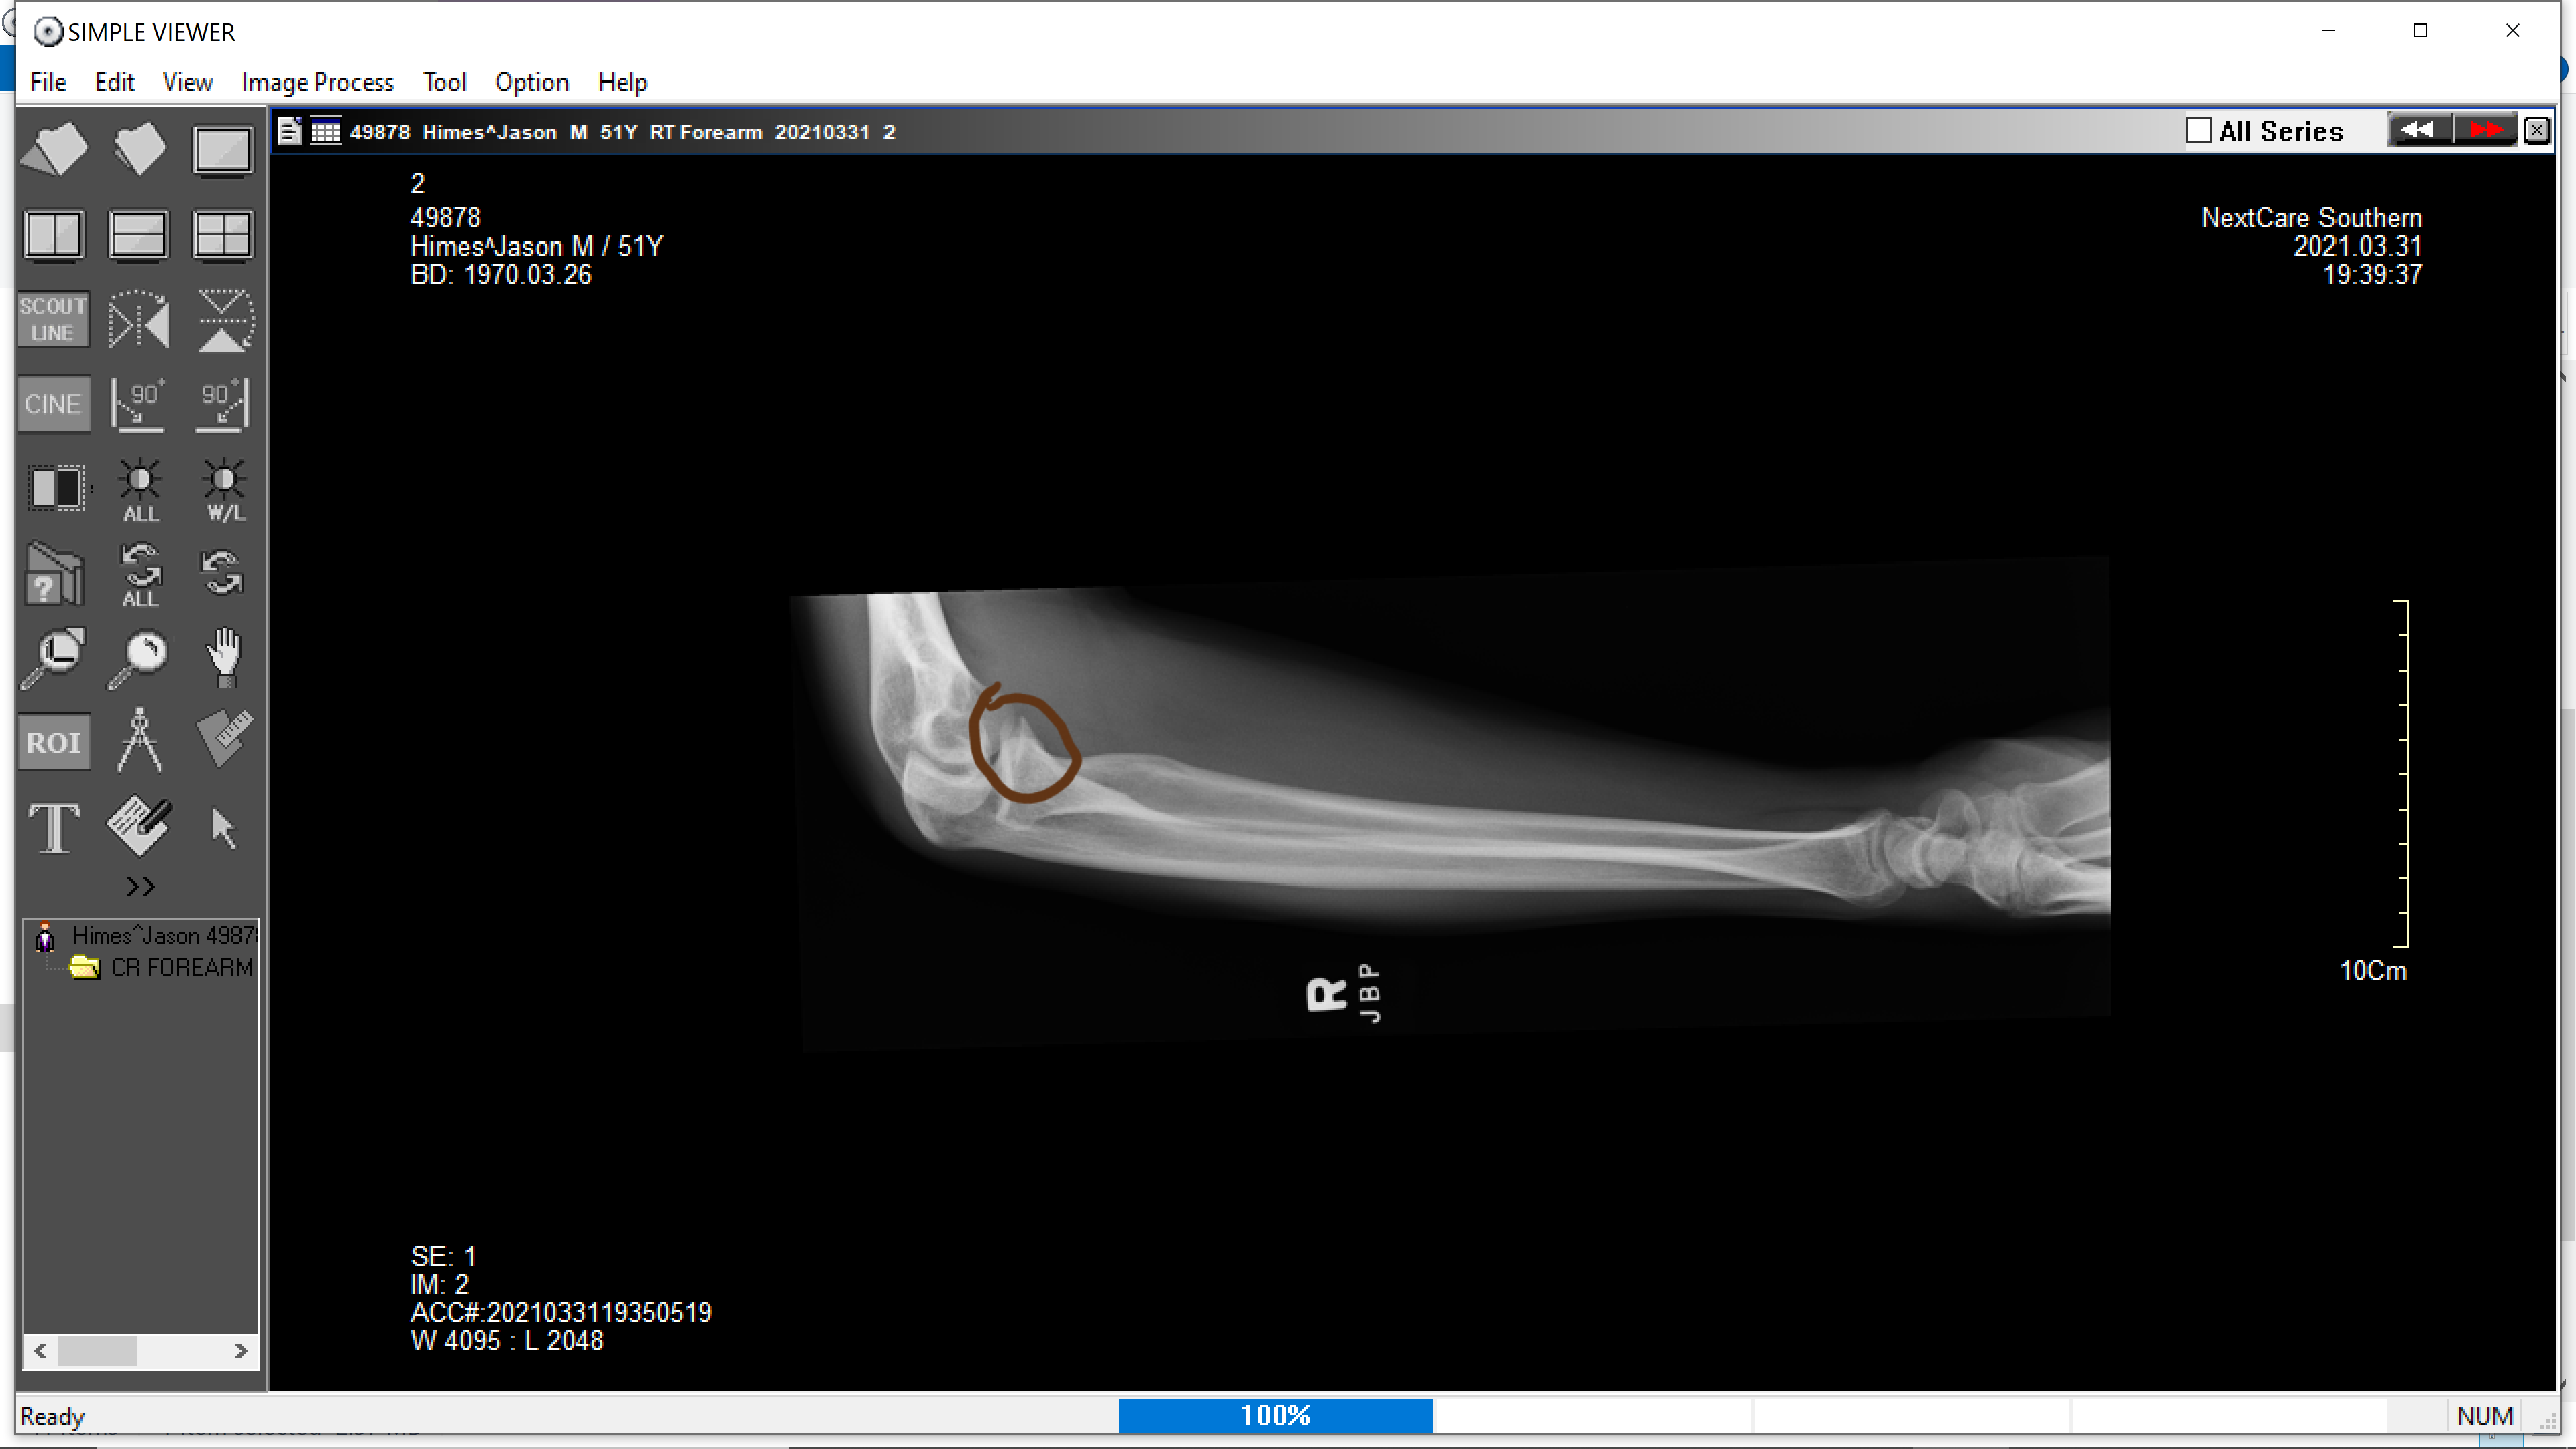

Yep, those look like bones.

I think I see it pretty clearly in the second image, right at the end or "head" of my radius. Right at the elbow. Looks like a compression fracture, which was my suspicion from the way I caught myself in the fall. I landed on my hand and never really hit my arm or elbow.

2021-04-02 07.18.28.png